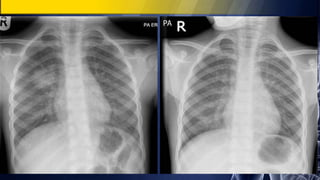

57-year-old woman with cough, hemoptysis and weight loss

• PA chest radiographs demonstrate a large right hilar mass with associated upper lobe

volume loss. Note the reverse “S” shape produced by the concave outline of the lateral

aspect of the minor fissure and the convex outline of the central mass, the so-called reverse

“S” sign of Golden.

• Contrast-enhanced chest CT (lung and mediastinal windows) reveals a large central mass

that produces severe irregular narrowing of the right main bronchus, atelectasis of the right

upper lobe, and deformity of the superior vena cava consistent with local invasion

Lung Cancer